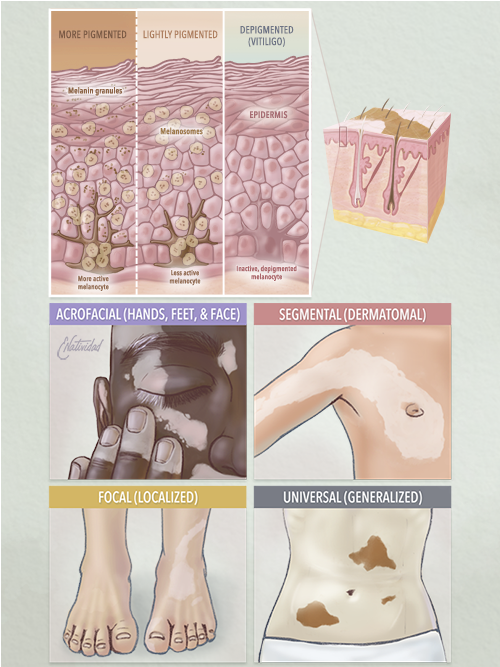

Running series of animated visual abstracts, Quick Takes, created for The New England Journal of Medicine as part of a team of illustrators, medical writers, and scientists. These short, iconographic animations aim to succinctly describe clinical trials and increase the awareness and understanding of important research findings.

Adopting The Journal’s visual style and asset library, I am responsible for the entire production process including narration editing, storyboarding, layout, illustration, and animation.